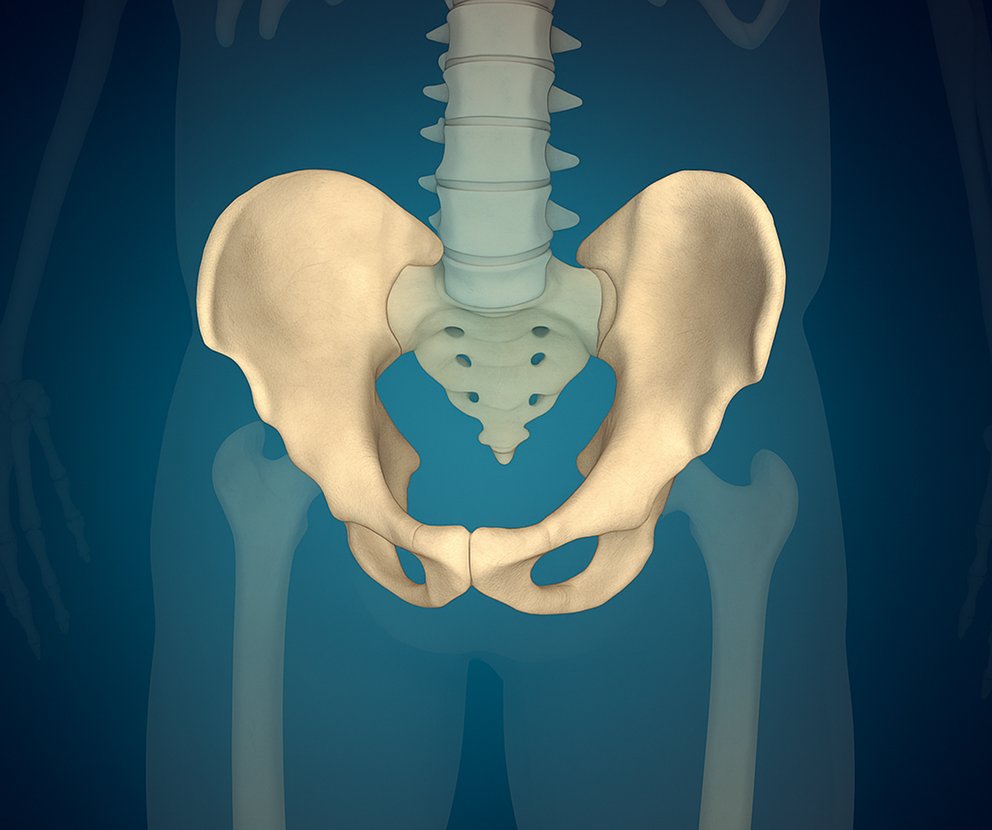

Restores Pelvic Stability & Function

Reconstructive surgery realigns and repairs pelvic structures, ensuring proper support for movement and daily activities.

Supports Long-Term Mobility & Health

Reconstructed pelvic structures reduce the risk of future complications and help maintain an active, independent lifestyle.